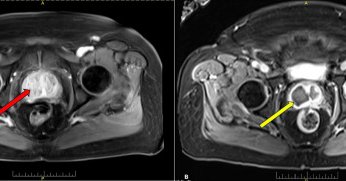

i know glue is all the rage but check out the staining in the L hemiprostate using particles during an injection from the RPA…159cc gland, used 36cc total (21cc on the left)! #irad #perfected

2